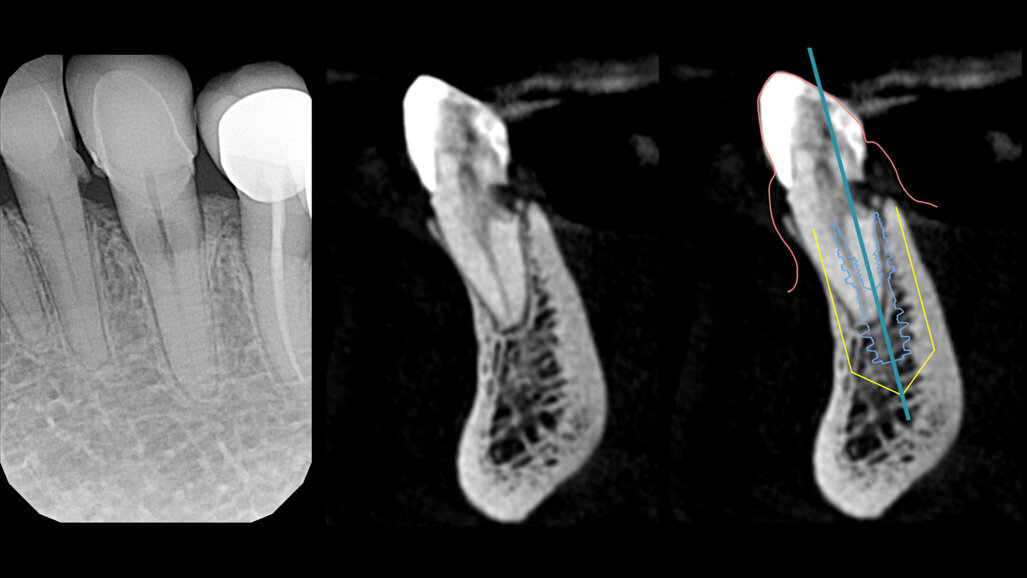

L’esame di primo livello (radiografia endorale) mostra la presenza di un minus dei tessuti calcificati a carico della radice. Si impone per ovvie ragioni un approfondimento volumetrico 3D: soltanto una CBCT ci consentirà di localizzare correttamente la lesione e valutarne la posizione, l’estensione e l’eventuale recuperabilità dell’elemento dentario. Il taglio trasversale della radiografia 3D mostra un riassorbimento radicolare esterno che riguarda la porzione linguale dell’elemento dentario (Figg. 1-4). Il riassorbimento presenta una posizione particolarmente sfavorevole, in quanto si estende già al di sotto del margine osseo crestale su un elemento dentario peraltro già trattato da un punto di vista protesico (Figg. 2, 3). Le opzioni terapeutiche proposte alla paziente sono sostanzialmente due: trattamento endodontico e rifacimento del restauro protesico, previo accesso chirurgico sul lato linguale con allungamento di corona clinica, oppure impianto post-estrattivo con tecnica Socket-Shield. La paziente sceglie questa seconda opzione e firma regolare consenso informato.

Fig. 4_Rx 2d e 3D, con evidenziazione del riassorbimento radicolare, che riguarda l’aspetto linguale e si approfondisce al di sotto del margine della corticale ossea; pianificazione implantare su apposito software di progettazione.